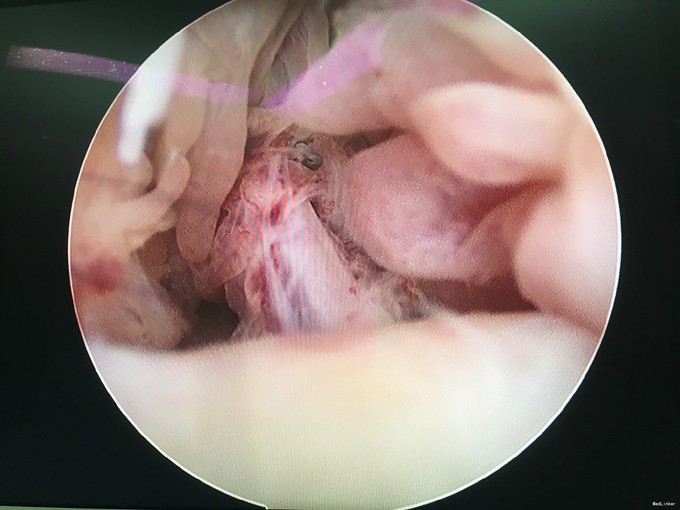

诊断:类风湿性关节炎 治疗:右膝关节镜下清理

随访:患者术后早期术膝肿胀消除明显,活动度较术前明显改善。患者继续至风湿免疫科行内科治疗。 讨论:对风湿性疾病的局部症状治疗,关节镜手术治疗不失为一实用而又有效的治疗方法。